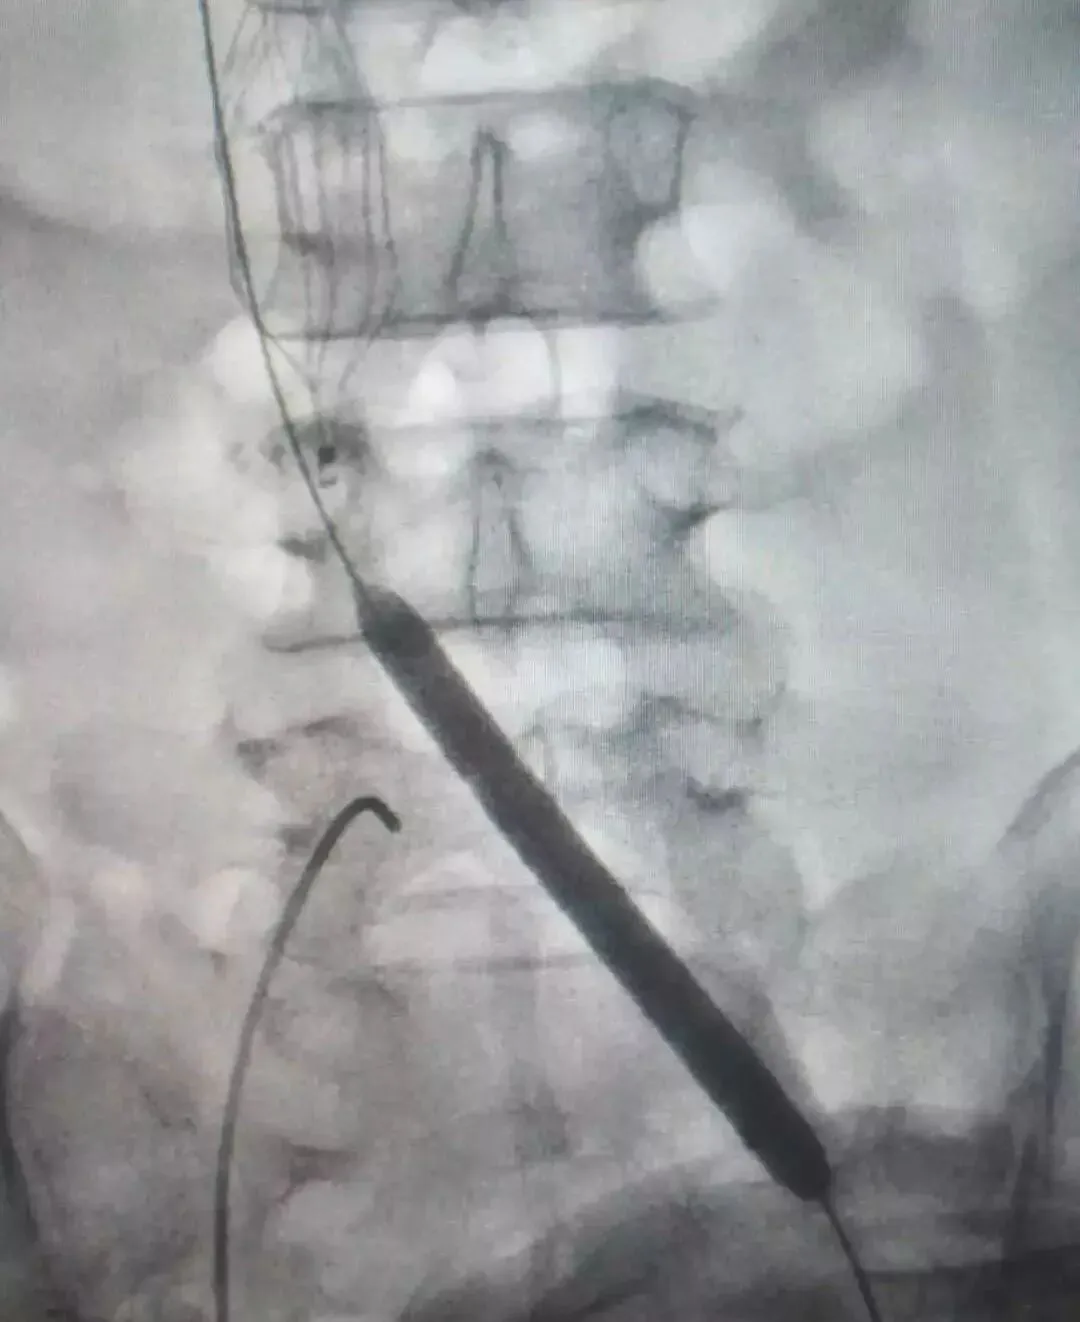

术中造影显示,王大叔左侧股静脉、髂总静脉有长段血栓形成,阻塞范围约有30cm长。由于静脉的血管壁薄,血管闭塞时间长,病变范围广,所以手术的风险极高。丛海波院长和影像科主任兼介入、血管外科负责人侯红军团队决定为其进行“左股静脉切开取栓+左髂总静脉闭塞球囊扩张术”,术中用取栓导管取出40-50毫升血栓,由于髂总静脉开口处血管质地硬,导管无法直接通过,采用导丝导管技术通过了闭塞段,并用球囊逐级扩张。

(球囊扩张过程)